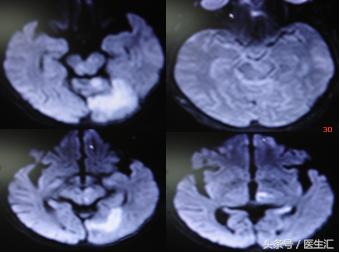

辅助检查:1、16:26CT检查平扫和灌注成像均未见明显异常(见图10、11)

2、头颅MRI、MRA及脑血管三维重建(图12、13、14)